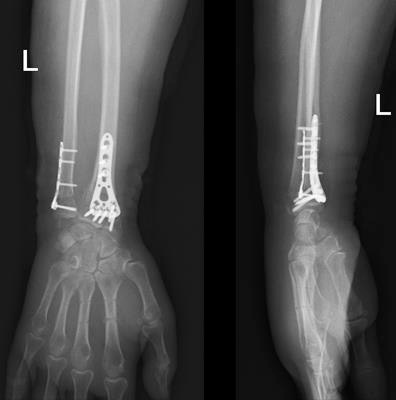

На 3 сутки выполнена открытая репозиция и фиксация переломов пластинами и винтами. Положение отломков удовлетворительное, пациентка выписана на амбулаторное лечение.